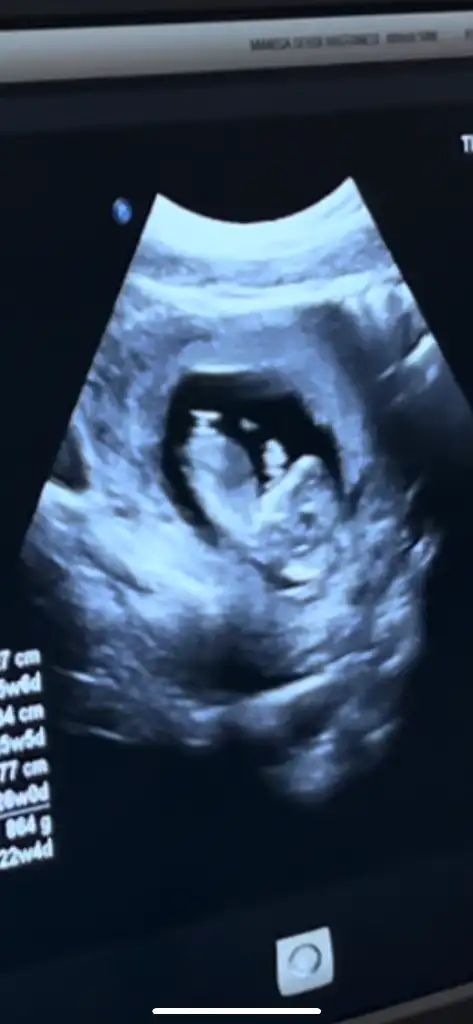

Kızlar sizce nuba göre cinsiyet nedir 12+5

• IMG_2188.webp

24 KB · Görüntüleme: 726